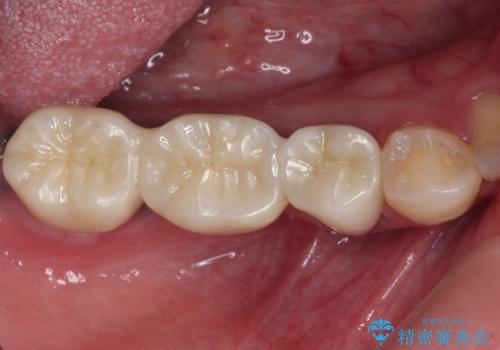

臼歯部メタルフリー再補綴